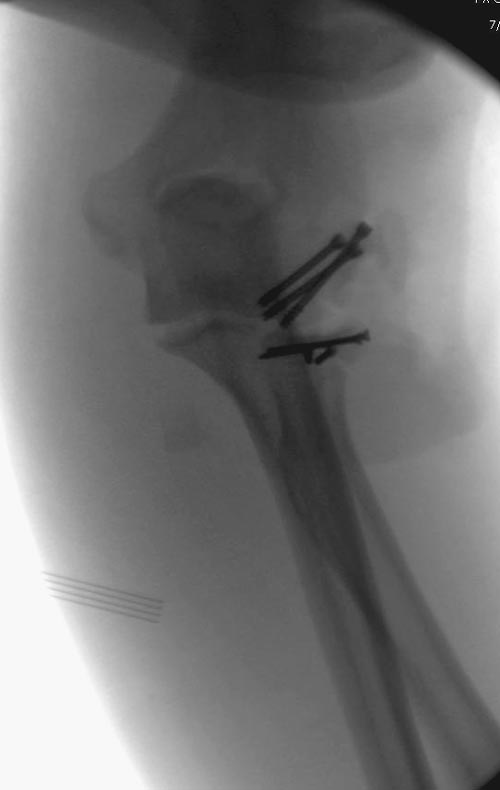

В первом случае перелом Монтеджи, где доперационно сделано оценка положения головки к остальным элементам под рентгеном. Учитывая правильность взаимотношении произведена фиксация только локтевого отростка, Второй случай, заменена на протез, и третий, кроме фиксации головки - реконструкция capitellum латерального мыщелка.

На представленных снимках есть смещение суставной поверхности. Принцип лечения внутрисуставных переломов - восстановление суставной поверхности. У нас есть опыт восстановления таких переломов микровинтами. Удачи!

Популярная в странах СНГ резекция головки луча в наших условиях делается очень редко, потому что без упора луча могут проявиться симптомы нестабильности в дистальном радио-ульнарном сочленении. Реконструкция с сохранением головки дает лучший результат, но не всегда возможна.